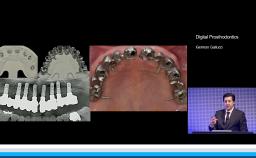

German Gallucci

Boston, United States